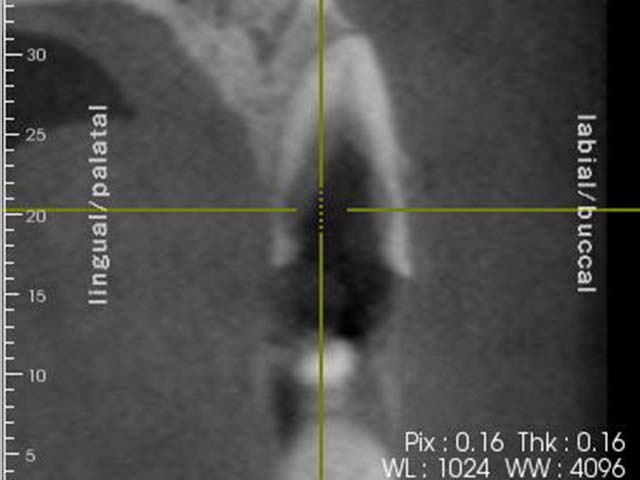

齒槽骨保存術+植牙 首頁 案例分享 人工植牙 齒槽骨保存術+植牙 STEP1拔除掉無法使用的斷裂牙根 STEP2齒槽骨保存術—使用骨粉填補拔牙傷口 術前 V.S 術後 植牙第一階段—植入牙根 植牙第二階段—製作正式假牙